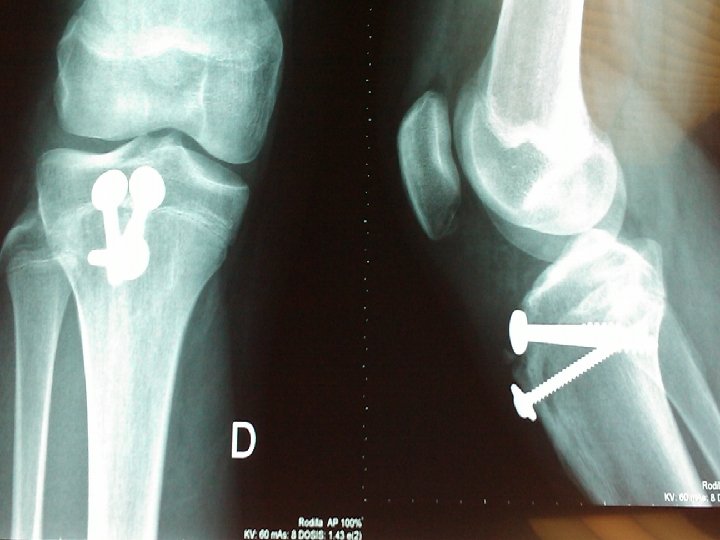

Caso clínico Nº 2 • Varón de 14 años • Dolor e impotencia funcional en rodilla dcha. Tras realizar un salto brusco haciendo deporte • No alergias medicamentosas conocidas • Sin antecedentes médicos de interés • No IQ • Práctica deportiva intensa

Exploración de rodilla dcha: Dolor en cara anterior con deformidad e impotencia funcional Pruebas complementarias: Rx rodilla dcha Arrancamiento tuberosidad tibial anterior

AVULSIÓN TRAUMÁTICA AGUDA DE LA TUBEROSIDAD TIBIAL • Lesión aguda (con frecuencia en la práctica deportiva) • Dolor y tumefacción importante e inmediata • Con frecuencia imposibilidad para mantenerse en pie o caminar • Con frecuencia reducción abierta y fijación interna • Rápida consolidación y retorno a las actividades completas

TRATAMIENTO QUIRÚRGICO • Reducción abierta con fijación interna en todas las fracturas • Salvo en fracturas de pequeños fragmentos sin desplazamiento

CUIDADOS POSREDUCCIÓN Y PRONÓSTICO • Yeso inguinopédico durante 4 -6 semanas • Férula posterior durante la 8 -9 semana y ejercicios de fortalecimiento cuadricipital • Buen pronóstico tras adecuada reducción